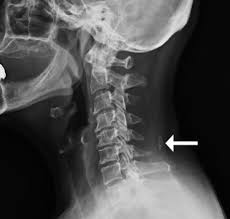

Ligamentum nuchae — das nackenband (ligamentum nuchae) ist ein paariges band aus elastischem bindegewebe, das als rückenseitige verspannung der halswirbelsäule dient. It covers the spines of c1 to c6 vertebrae. What does ligamentum nuchae mean? It runs from the external occipital protuberance along the tips of the spinous processes of the. Ligamentum nuchae — das nackenband (ligamentum nuchae) ist ein paariges band aus elastischem bindegewebe, das als rückenseitige verspannung der halswirbelsäule dient. The ligamentum nuchae is a large median ligament composed of tendons and fascia located between the posterior muscles of the neck. ( plural ligamenta nuchae ). It extends from the external occipital protuberance and median.

This ligament connects under the facet joints to create a small curtain over the posterior. The ligamentum nuchae are very strong. Looking for online definition of ligamentum nuchae in the medical dictionary? In chiari malformation treatment, decompression and duraplasty with a harvested ligamentum nuchae showed similar outcomes to pericranial and artificial grafts.3. The ligamentum nuchae is a large median ligament composed of tendons and fascia located between the posterior muscles of the neck. Medical definition of ligamentum nuchae: It extends from the external occipital protuberance and median. Continuous with the supraspinous ligament. What does ligamentum nuchae mean? A layer of tissue that protects the spinal cord. The ligamentum flavum forms a cover over the dura mater: A median ligament of the back of the neck that is rudimentary in man but highly developed and. It runs from the external occipital protuberance along the tips of the spinous processes of the.

The ligamentum nuchae are very strong. Ligamentum nuchae — das nackenband (ligamentum nuchae) ist ein paariges band aus elastischem bindegewebe, das als rückenseitige verspannung der halswirbelsäule dient. A median ligament of the back of the neck that is rudimentary in man but highly developed and. The ligamentum flavum forms a cover over the dura mater: The ligamentum nuchae is a ligament that forms a strong, fibrous median partition between the muscles of the two sides of the back of the neck.